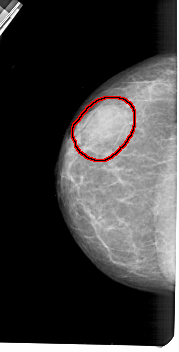

FILE: A_1419_1.LEFT_CC.OVERLAY

TOTAL_ABNORMALITIES 1

ABNORMALITY 1

LESION_TYPE MASS SHAPE OVAL MARGINS OBSCURED

ASSESSMENT 4

SUBTLETY 4

PATHOLOGY BENIGN

TOTAL_OUTLINES 1

BOUNDARY